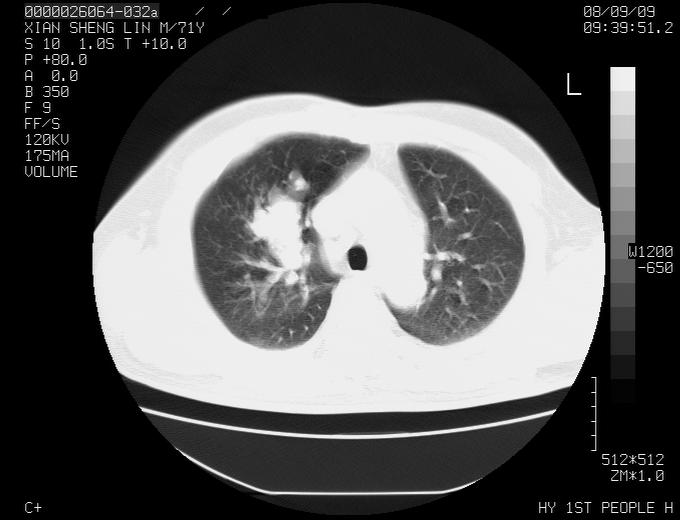

标题: CT15869:男性,71岁,因咳嗽而就诊,请讨论右上肺病变性质 [打印本页]

标题: CT15869:男性,71岁,因咳嗽而就诊,请讨论右上肺病变性质

患者,男性,71岁,因咳嗽而就诊,

肺癌并淋巴结转移。

右肺门淋巴结结核可能性大

考虑肺癌并淋巴结转移可能性大

典型的右肺中心性肺癌并纵隔淋巴结转移

右肺中心性肺癌并纵隔淋巴结转移可能性大!

右肺中心性肺癌并纵隔淋巴结转移可能性大! 支持!

病灶中等程度强化 还是支持肺癌诊断

考虑右肺中心性肺癌并右肺门及纵隔淋巴结转移。

1,右肺中心型ca,气管隆突旁淋巴结转移。

2,右膈明显抬高,建议肝脏扫描排除转移或原发灶。

支持右肺中心性肺癌并右肺门及纵隔淋巴结转移。